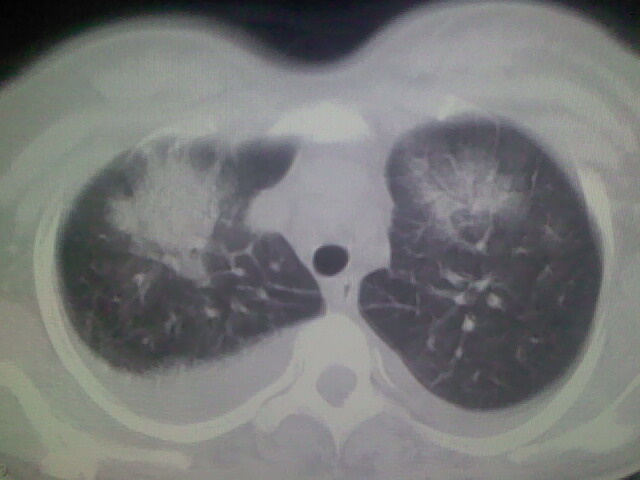

女,24,剖腹产后,突觉胸痛,干咳,不能平卧

双肺“肺泡性肺水肿” “胸腔积液”!

考虑肺梗塞、肺水肿,双侧胸腔积液

肺水肿,双侧胸腔积液,心影增大.考虑妊娠心脏病

考虑产后心肌病,心功能不全,肺水肿,双侧胸腔积液。

风心、心衰。两肺水肿、感染灶及胸水是心衰表现